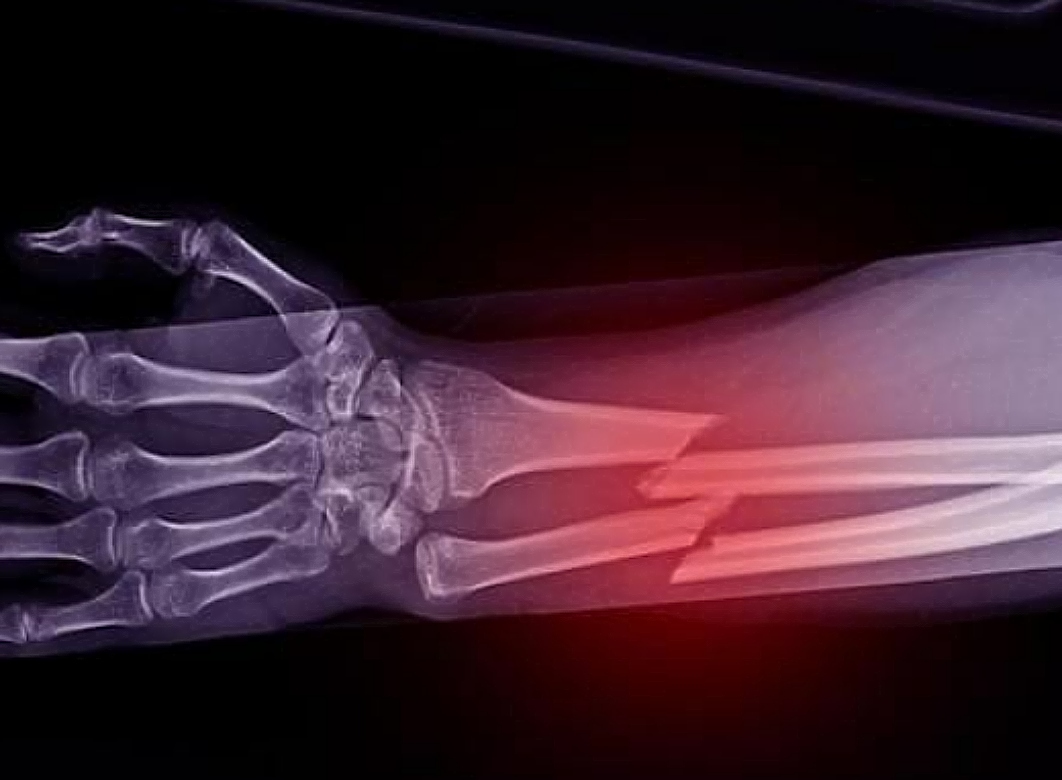

Για τους περισσότερους ανθρώπους, η παιδική ηλικία περιλαμβάνει πτώσεις από τις κούνιες, γλιστρήματα στις σκάλες ή χτυπήματα στον αστράγαλο κατά τη διάρκεια του παιχνιδιού, καταλήγοντας πολλές φορές στο νοσοκομείο με κάποιο σπασμένο κόκκαλο.

Για μερικούς πιο άτυχους, ένα ατύχημα στην ενήλικη ζωή μπορεί να οδηγήσει σε εβδομάδες με γύψο ή πατερίτσες. Αλλά τι γίνεται με εκείνους που δεν έχουν σπάσει ποτέ κόκκαλο; Αν ρωτήσουμε τους πνευματιστές, το να μην έχεις σπάσει ποτέ κόκκαλο θεωρείται «θείο δώρο» ή ένδειξη ότι πλησιάζεις στο τέλος του κύκλου μετενσάρκωσης.

Όπως συμβαίνει με πολλά πράγματα, η γενετική μπορεί να παίζει ρόλο στο γιατί δεν έχετε σπάσει ποτέ τον αστράγαλό σας ή δεν έχετε πάθει κάταγμα στον καρπό σας.

Η γενετική επηρεάζει τη δύναμη των οστών, με ορισμένους ανθρώπους να αναπτύσσουν γενετικές μεταλλάξεις που τους επιτρέπουν να έχουν εξαιρετικά πυκνά κόκκαλα. Αντίθετα, όσοι έχουν οικογενειακό ιστορικό οστεοπόρωσης ή άλλων παθήσεων των οστών διατρέχουν μεγαλύτερο κίνδυνο για χαμηλή οστική πυκνότητα.